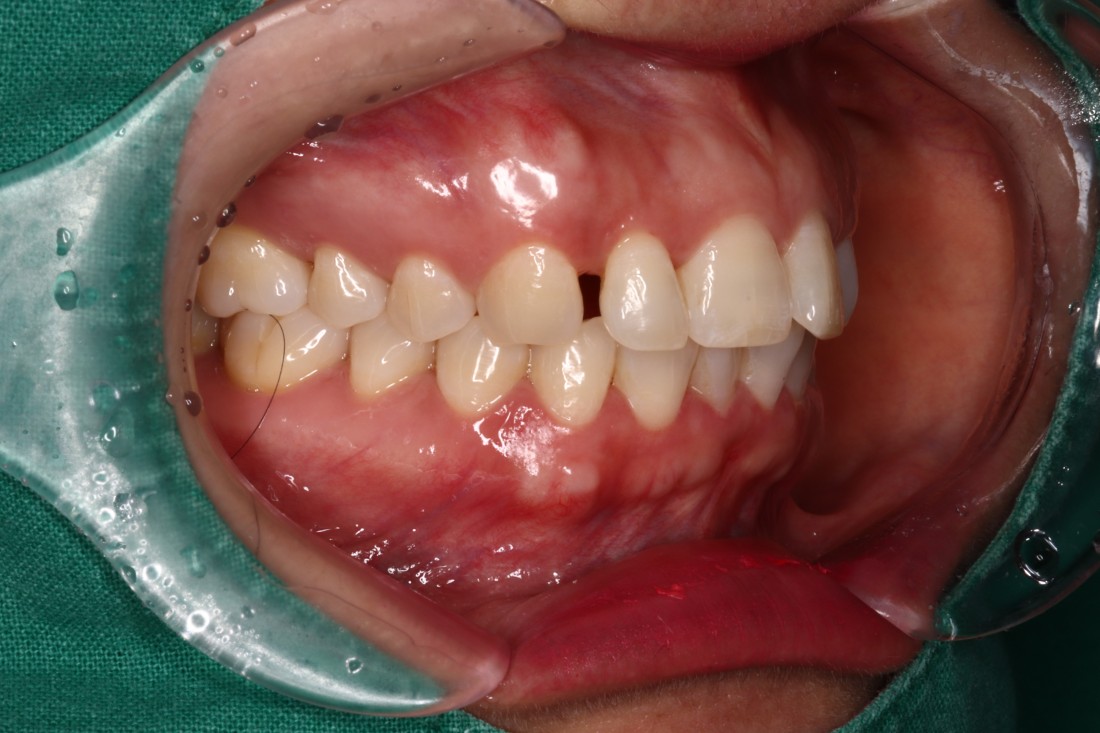

광주 앞니교정 앞니부분교정이나 급속앞니교정을 원할 때는 바로 이 진료를 추천합니다